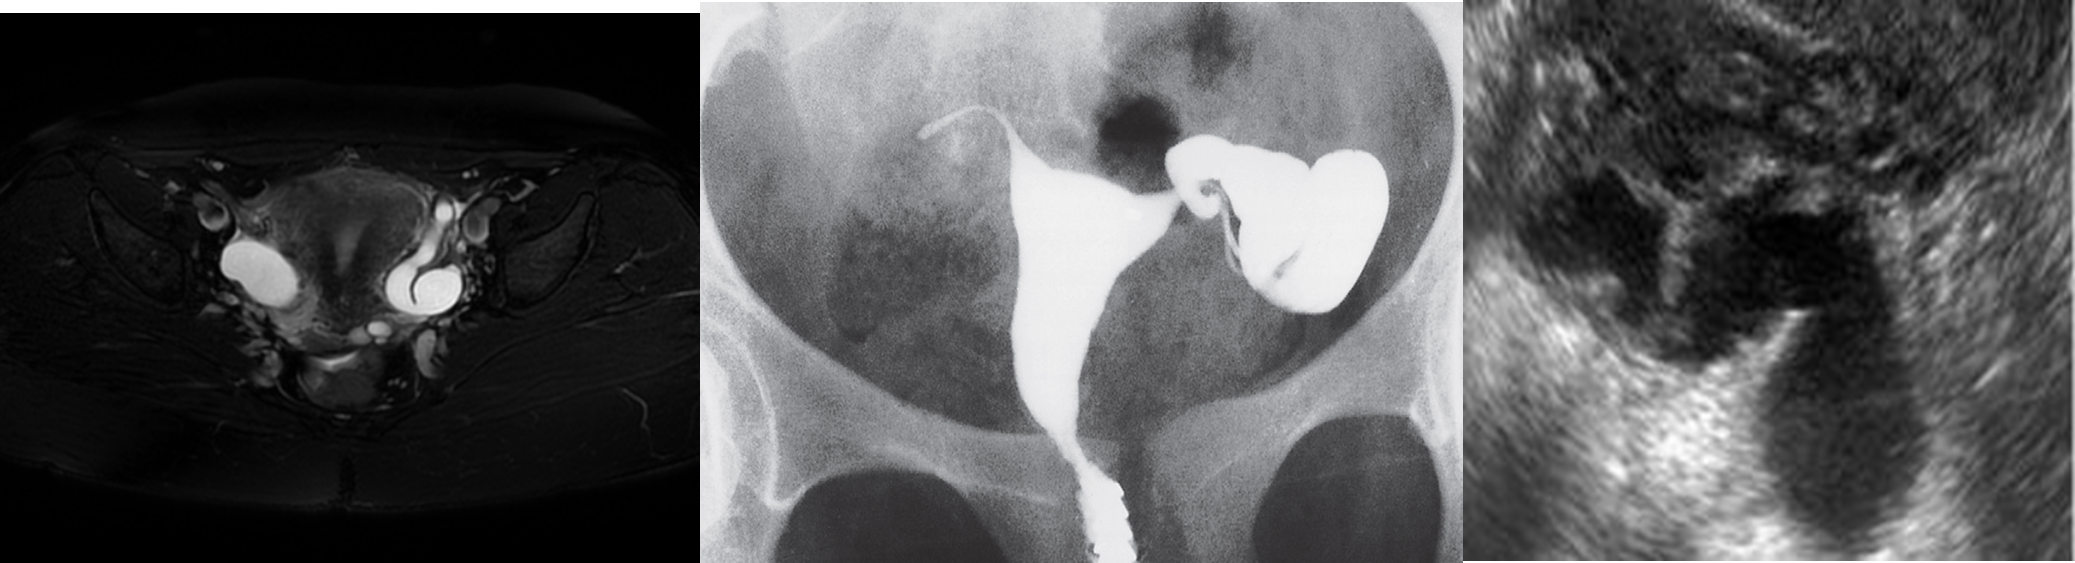

Block and dilated fallopian tubes with fluid.

Ultrasound shows block tube causing hydrosalpinx